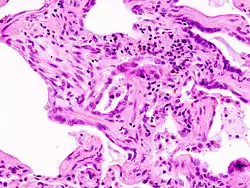

![]() | |

| End-stage pulmonary fibrosis of unknown origin, taken from an autopsy | |

Thirty to 40% of those with interstitial lung disease eventually develop pulmonary fibrosis which has a median survival of 2.5-3.5 years.[10] Idiopathic pulmonary fibrosis is interstitial lung disease for which no obvious cause can be identified (idiopathic) and is associated with typical findings both radiographic (basal and pleural-based fibrosis with honeycombing) and pathologic (temporally and spatially heterogeneous fibrosis, histopathologic honeycombing, and fibroblastic foci).

A lung biopsy may be required if the clinical history and imaging are not clearly suggestive of a specific diagnosis or malignancy cannot otherwise be ruled out. Surgical lung biopsy or via a video-assisted thoracoscopic surgery (VATS) biopsy is associated with a mortality rate up to 1-2%. A bronchoscopic transbronchial cryobiopsy, in which a camera is introduced into the airways followed by rapid freezing of an area of lung tissue prior to biopsy is associated with a lower complication rate and a much lower mortality rate compared to VATS or surgical biopsy with near comparable diagnostic accuracy.[17] There are four types of histopathologic patterns seen in ILD: usual interstitial pneumonia, non-specific interstitial pneumonia, organizing pneumonia, and diffuse alveolar damage.[10] There is significant overlap of the histopathological and radiologic features of each ILD type making diagnosis challenging; even with lung biopsy, 15% of cases of ILD cannot be classified.[10]